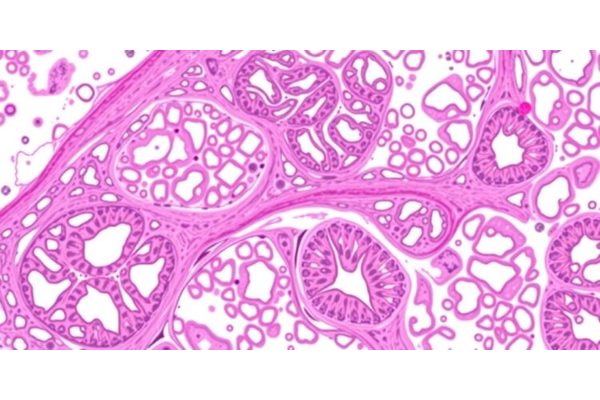

Home Science News Biology New Study Reveals Striking Parallels Between Atherosclerosis and Tumor Development June 17, 2025 in Biology Reading Time: 4 mins read 0 67 SHARES 606 VIEWS Share on